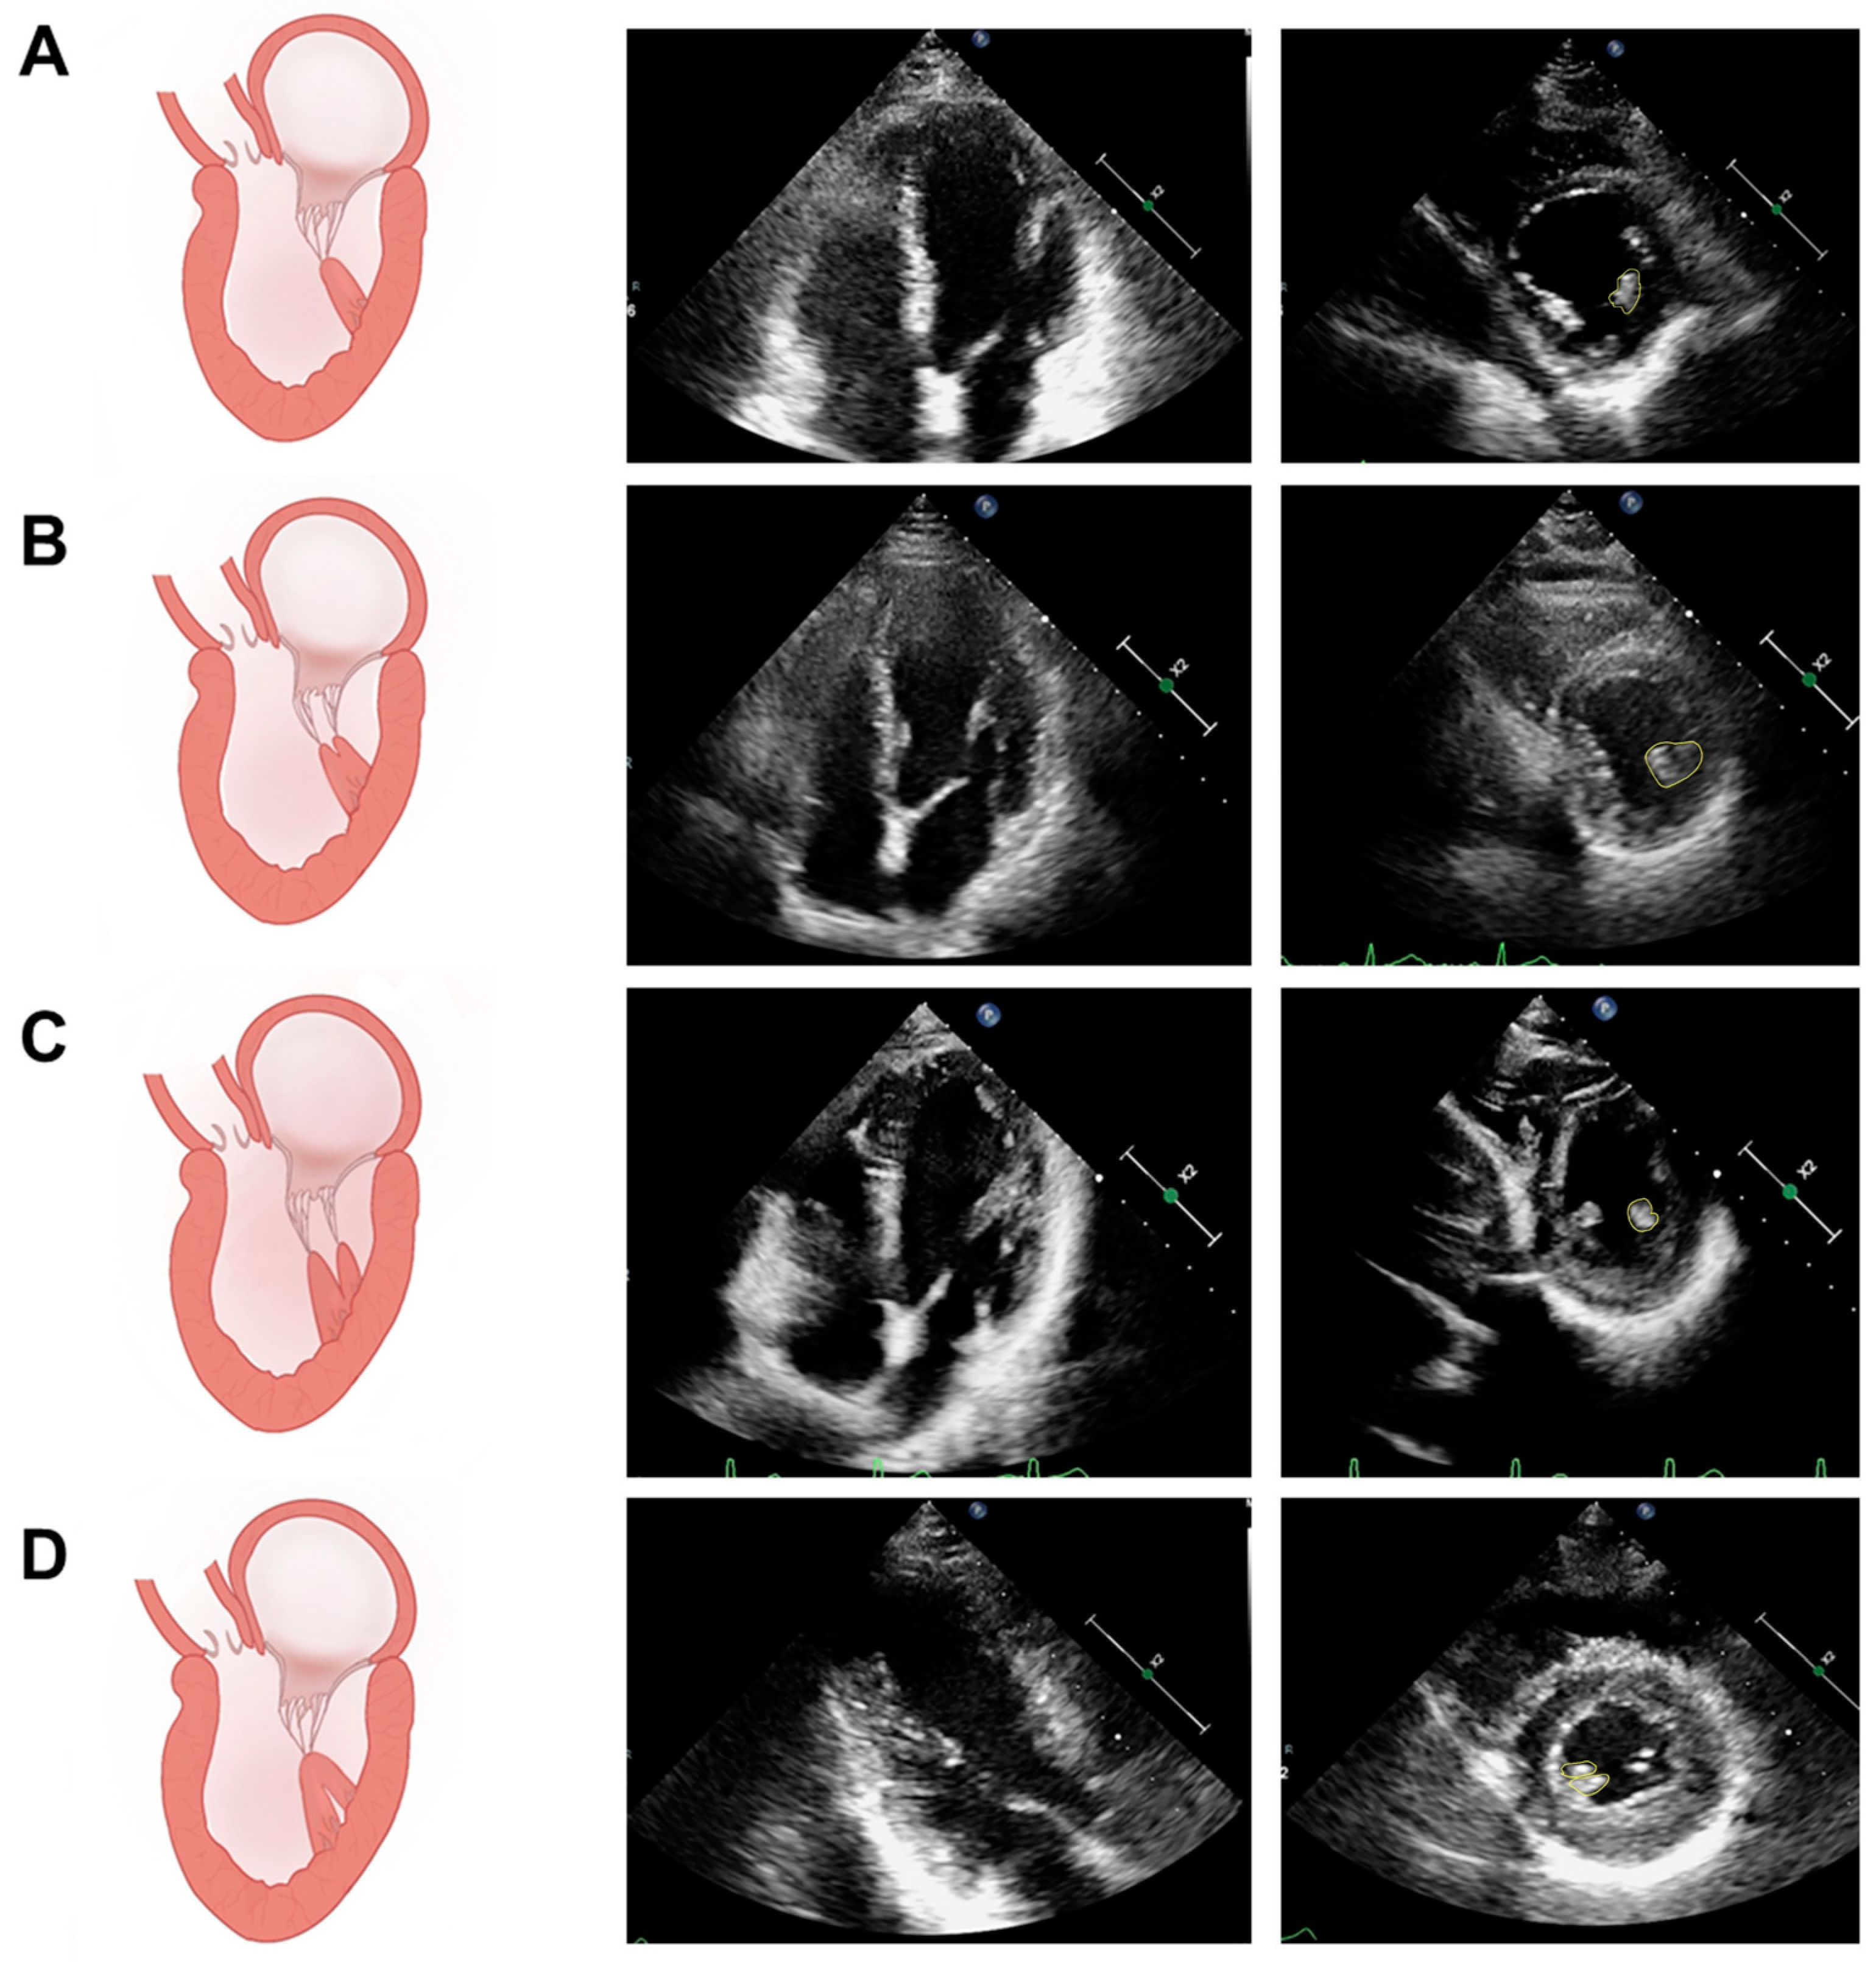

2.1. PM Structure and Variation

5.1. Assessment of PM Structure